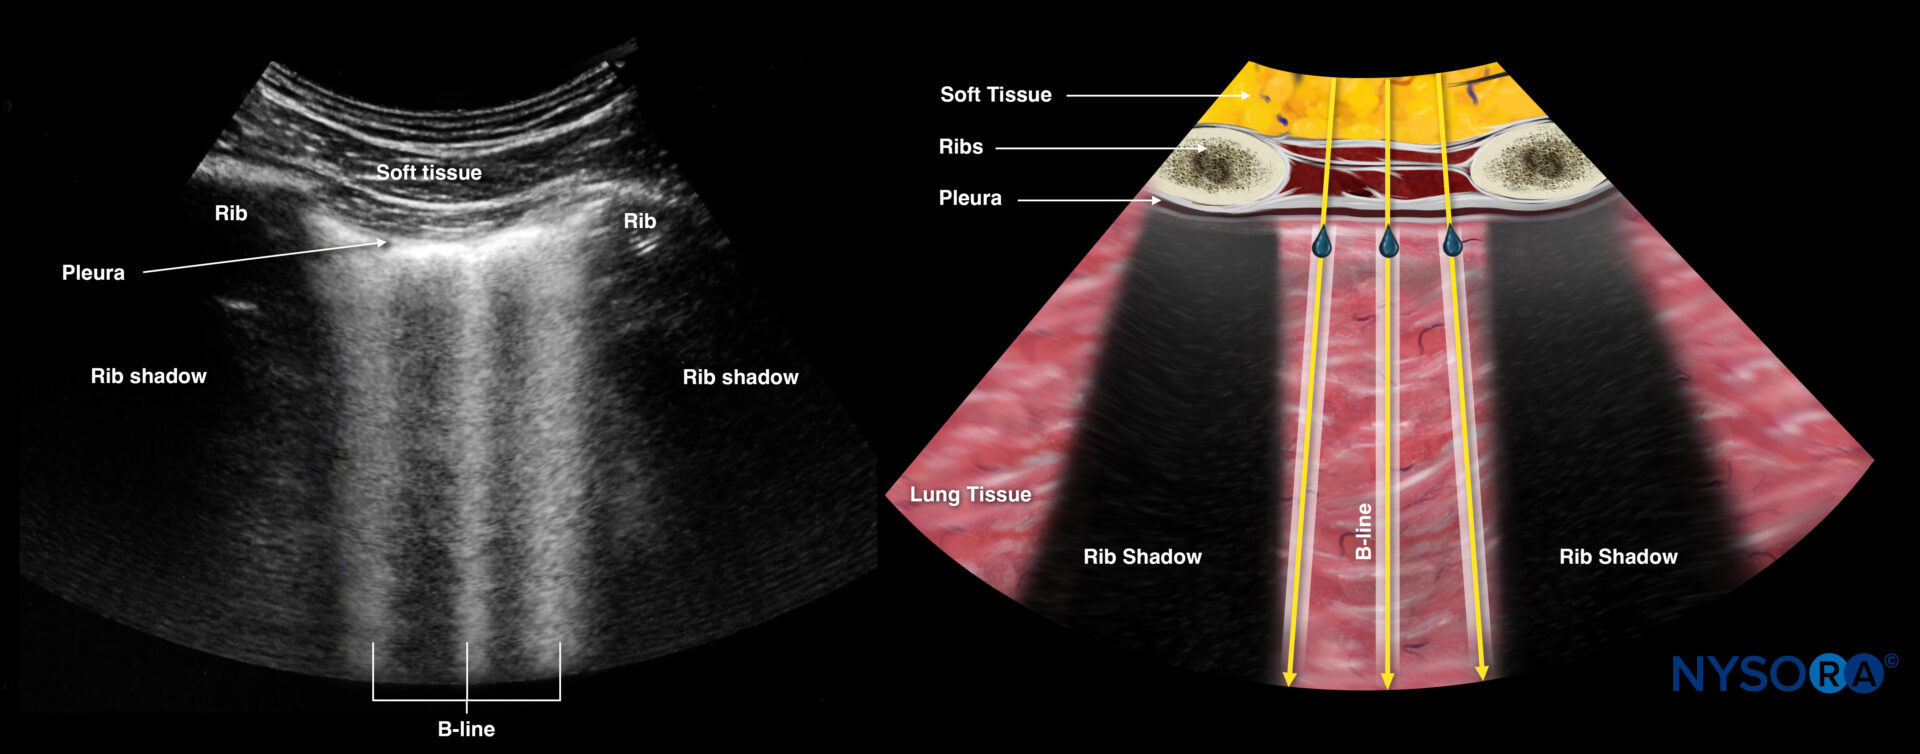

Left & right lung

These views allow assessment of the right and left lung for pneumothorax.

- Position the transducer on the left and right anterior chest wall, just below the clavicle (2nd-3rd intercostal space), and on the midclavicular line with the orientation marker toward the head of the patient.

Normal vs. abnormal sonoanatomy:

While the transducer is in these positions, assess the lungs for the following signs:

- Bat sign = two adjacent ribs with pleura in between.

The bat sign indicates the position of the transducer between two ribs and the ability to image the lung surface as well as deeper structures. This should always be the first step that makes sure you are in the correct position to address the pleura and the underlying lung. It is called the “bat sign” since the ribs resemble the wings and the pleura resembles the body of the bat.

The bat sign is indicated in white: Two adjacent ribs with pleura in between.

- The presence of B-lines, a vertical line artifact over the full length of the ultrasound beam and obliterating the horizontal A-lines, also rules out a pneumothorax.

B-lines.